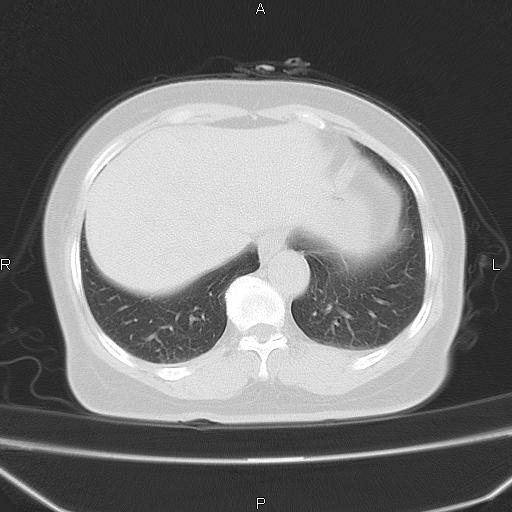

胸腺瘤

女、63Y 双眼睑下垂,早轻晚重。 胸腺瘤???

结果胸腺瘤